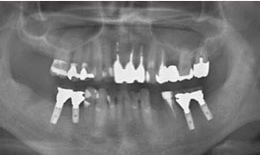

インプラント症例(20) 52歳 男性

治療前

治療後

保存困難な歯を抜歯後、インプラントを4本埋め込んで、セラミックスクラウンを被せた